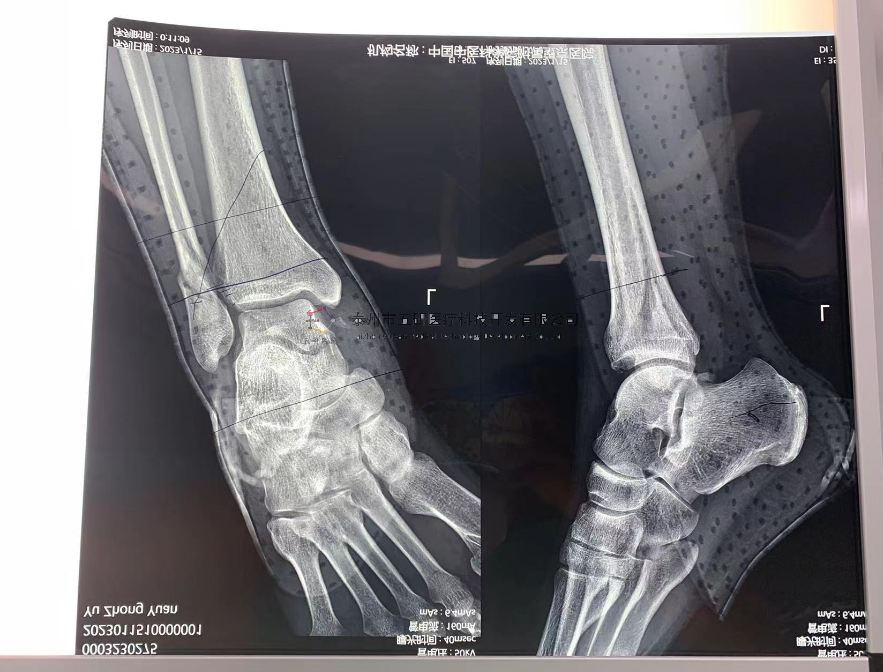

【治療后影像】

【手術(shù)資料】

3

// 下肢骨折

【所屬科室】中國(guó)中醫(yī)科學(xué)院望京醫(yī)院創(chuàng)一科

【基本資料】患者,男,65歲

【患者情況】脛骨遠(yuǎn)端骨折伴腓骨骨折

【影像圖片—術(shù)前】

【影像圖片—術(shù)后】